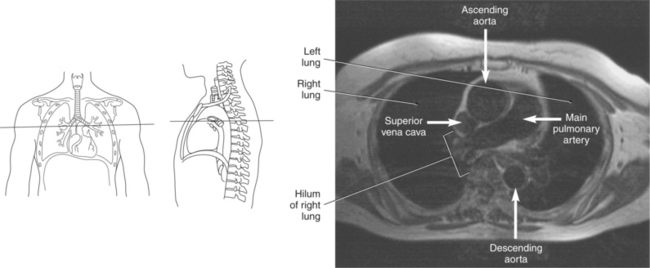

Blood travels to and from the heart through the great vessels, which include the aorta, pulmonary arteries and veins, and superior and inferior venae cavae (Figures 6.54 and 6.55). The aorta is the largest artery of the body and can be divided into the ascending aorta, aortic arch, and descending aorta. The ascending aorta begins at the base of the left ventricle at the level of the sternal angle, then curves superiorly and posteriorly as the aortic arch over the root of the left lung. The top of the aortic arch is approximately at T3 (Figures 6.56 and 6.57). The arch continues as the descending aorta posterior to the left bronchus and pulmonary trunk, on the left side of the vertebral body of T4 (Figures 6.58 and 6.59). The descending aorta passes slightly anterior and to the left of the vertebral column as it descends through the thoracic and abdominal cavities (Figure 6.60). While in the thoracic cavity, the descending aorta is commonly called the thoracic aorta, and while in the abdominal cavity, it is called the abdominal aorta. The pulmonary trunk is the origin of the right and left pulmonary arteries and lies entirely within the pericardial sac. It arises from the right ventricle and ascends in front of the ascending aorta, courses posteriorly and to the left, where it bifurcates at the level of the sternal angle (T4) into the right and left pulmonary arteries (Figures 6.61 through 6.63). The pulmonary trunk is attached to the aortic arch by a fibrous cord called the ligamentum arteriosum, the remnant of an important fetal blood vessel (ductus arteriosus) that links the pulmonary and systemic circuits during fetal development (Figures 6.54 and 6.61). The right pulmonary artery courses laterally, posterior to the ascending aorta and superior vena cava, and anterior to the esophagus and right mainstem bronchus, to the hilum of the right lung. At the root of the right lung, the right pulmonary artery divides into two branches, with the lower branch supplying the middle and inferior lobes and the upper branch supplying the superior lobe (Figures 6.61 through 6.64). The left pulmonary artery, shorter and smaller than the right, is also the most superior of the pulmonary vessels. It travels horizontally, arching over the left mainstem bronchus, and enters the hilum of the left lung just superior to the left mainstem bronchus (Figures 6.61 through 6.64). Within the lungs, each pulmonary artery descends posterolateral to the main bronchus and divides into lobar and segmental arteries, continuing to branch out and to follow along with the smallest divisions of the bronchial tree (Figures 6.61 and 6.64). Located inferior to the pulmonary arteries are the four pulmonary veins, two each (superior and inferior) extending from each lung to enter the left atrium (Figures 6.54, 6.55, 6.61, and 6.64 through 6.68). They commence in a capillary network along the walls of the alveoli, where they are continuous with the capillaries of the pulmonary arteries. The venous capillaries merge to form small vessels that unite successively to eventually form a single trunk for each lobe: three for the right and two for the left lung. Frequently the trunk from the middle lobe of the right lung unites with the trunk from the upper lobe, forming just two trunks on the right side prior to entering the left atrium. The right superior pulmonary vein collects blood from the upper lobe segments of the right lung and passes anterior and inferior to the right pulmonary artery, behind the superior vena cava. The right inferior pulmonary vein receives blood from the right lower lobes of the lung and crosses behind the right atrium to the left atrium (Figures 6.61 and 6.69 through 6.71). The left superior pulmonary vein receives blood from the left upper lobe of the left lung and courses anterior and inferior to the left main bronchus as it enters the left atrium. The left inferior pulmonary vein drains the inferior lobe of the left lung and passes toward the left atrium anterior to the bronchi (Figures 6.61 and 6.72 through 6.74). The pulmonary veins course more horizontally than the pulmonary arteries and are ultimately oriented toward the left atrium. At the root of the lungs, the pulmonary veins are anterior to the pulmonary arteries, which are anterior to the bronchus. While within the lungs, the branches of the pulmonary arteries are anterior to the bronchi, which are anterior to the pulmonary veins. The superior and inferior venae cavae are the largest veins of the body. The superior vena cava is formed by the junction of the brachiocephalic veins, posterior to the right first costal cartilage, and carries blood from the thorax, upper limbs, head, and neck (Figure 6.24). As it travels inferiorly, it is located posterior and lateral to the ascending aorta before entering the upper portion of the right atrium (Figures 6.54 through 6.59). The inferior vena cava is formed by the junction of the common iliac veins in the pelvis and ascends the abdomen to the right of the abdominal aorta and anterior to the vertebral column. It passes through the caval hiatus of the diaphragm and almost immediately enters the inferior portion of the right atrium (Figures 6.75 and 6.76).